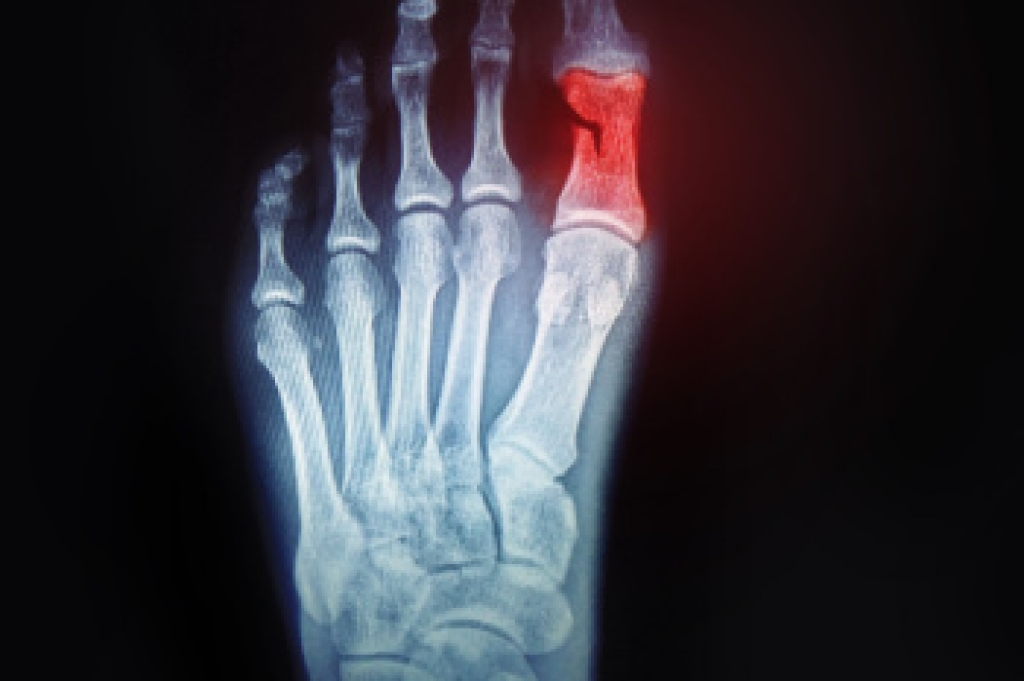

Identifying a broken toe is important for timely treatment and recovery. One of the primary signs is a noticeable change in the toe's shape, as it may appear misaligned, crooked, or deformed. Severe pain is another common indicator, often sharp and intense at the moment of injury and persisting with movement. The affected toe might also show swelling and bruising, with discoloration appearing as a dark purple or blue hue. In some cases, there may be difficulty or discomfort when trying to move the toe. Prompt medical evaluation is essential for proper diagnosis and treatment, which may include rest, immobilization, or in severe cases, surgical intervention. If you have broken your toe, it is suggested that you consult a podiatrist who can offer you the correct treatment.

Broken toes may cause a lot of pain and should be treated as soon as possible. If you have any concerns about your feet, contact our podiatrists from Superior Foot & Ankle Center. Our doctors will treat your foot and ankle needs.

What Is a Broken Toe?

A broken toe occurs when one or more of the toe bones of the foot are broken after an injury. Injuries such as stubbing your toe or dropping a heavy object on it may cause a toe fracture.

Symptoms of a Broken Toe

Although the injured toe should be monitored daily, it is especially important to have a podiatrist look at your toe if you have severe symptoms. Some of these symptoms include worsening or new pain that is not relieved with medication, sores, redness, or open wounds near the toe.

If you have any questions please feel free to contact our office located in Long Beach, CA . We offer the newest diagnostic tools and technology to treat your foot and ankle needs.